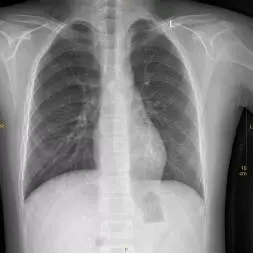

这是一张标准胸片

一张合格的胸片是不允许有任何体外异物的,因为任何异物的存在都会影响诊断。

我们来看看一些反面例子。

这是带有伪影干扰的胸片